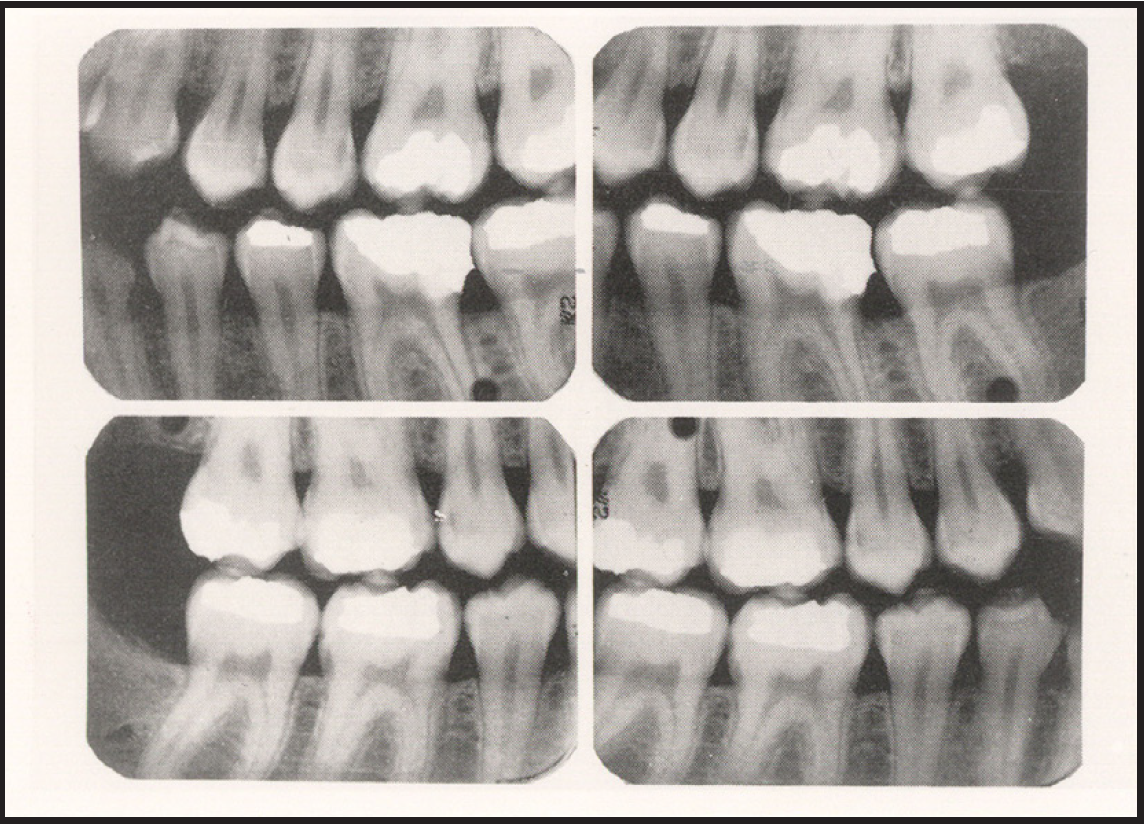

The selection of receptor sizes used in a full mouth series also varies. A full survey can consist of narrow anterior (type 1); standard adult (type 2); type 2 bitewing or long bitewing (type 3) (Figure 4) and may include anterior bitewings. It is generally recommended to use twenty radiographic images --- four bitewings and sixteen periapical images. Eight anterior type 1 radiographic images will allow for ease of receptor placement on patients with narrow palates. However, in some cases six anterior periapical images will cover the area needed.

When using type 3 receptors, only one longer bitewing is used on each side. Opening both the premolar and molar contacts on one radiographic image can be very difficult (Figure 5). With the use of type 2 receptors for bitewings, the operator uses a total of four images. Each image is assigned either premolars or molars (Figure 6). Use of the type 2 instead of type 3 radiographic receptors for bitewings is not only more comfortable for the patient but is easier for the operator to open the contacts.

Figure 4 - Intraoral Receptor Sizes

Figure 4

Figure 5 - Full Mouth Series using type 3 Bitewings

Figure 5

Figure 6 - Full Mouth Series using type 2 Bitewings

Figure 6